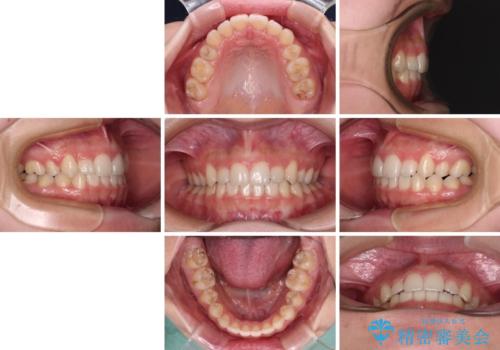

目立つ八重歯を目立たない装置で ハーフリンガルによる抜歯矯正

治療期間の目安は2年半~3年間でしたが、予定通り治療が進み、2年半弱で終えることができました。

歯列はきれいに整い、治療期間も予定通りであり、患者様には大変満足していただきました。